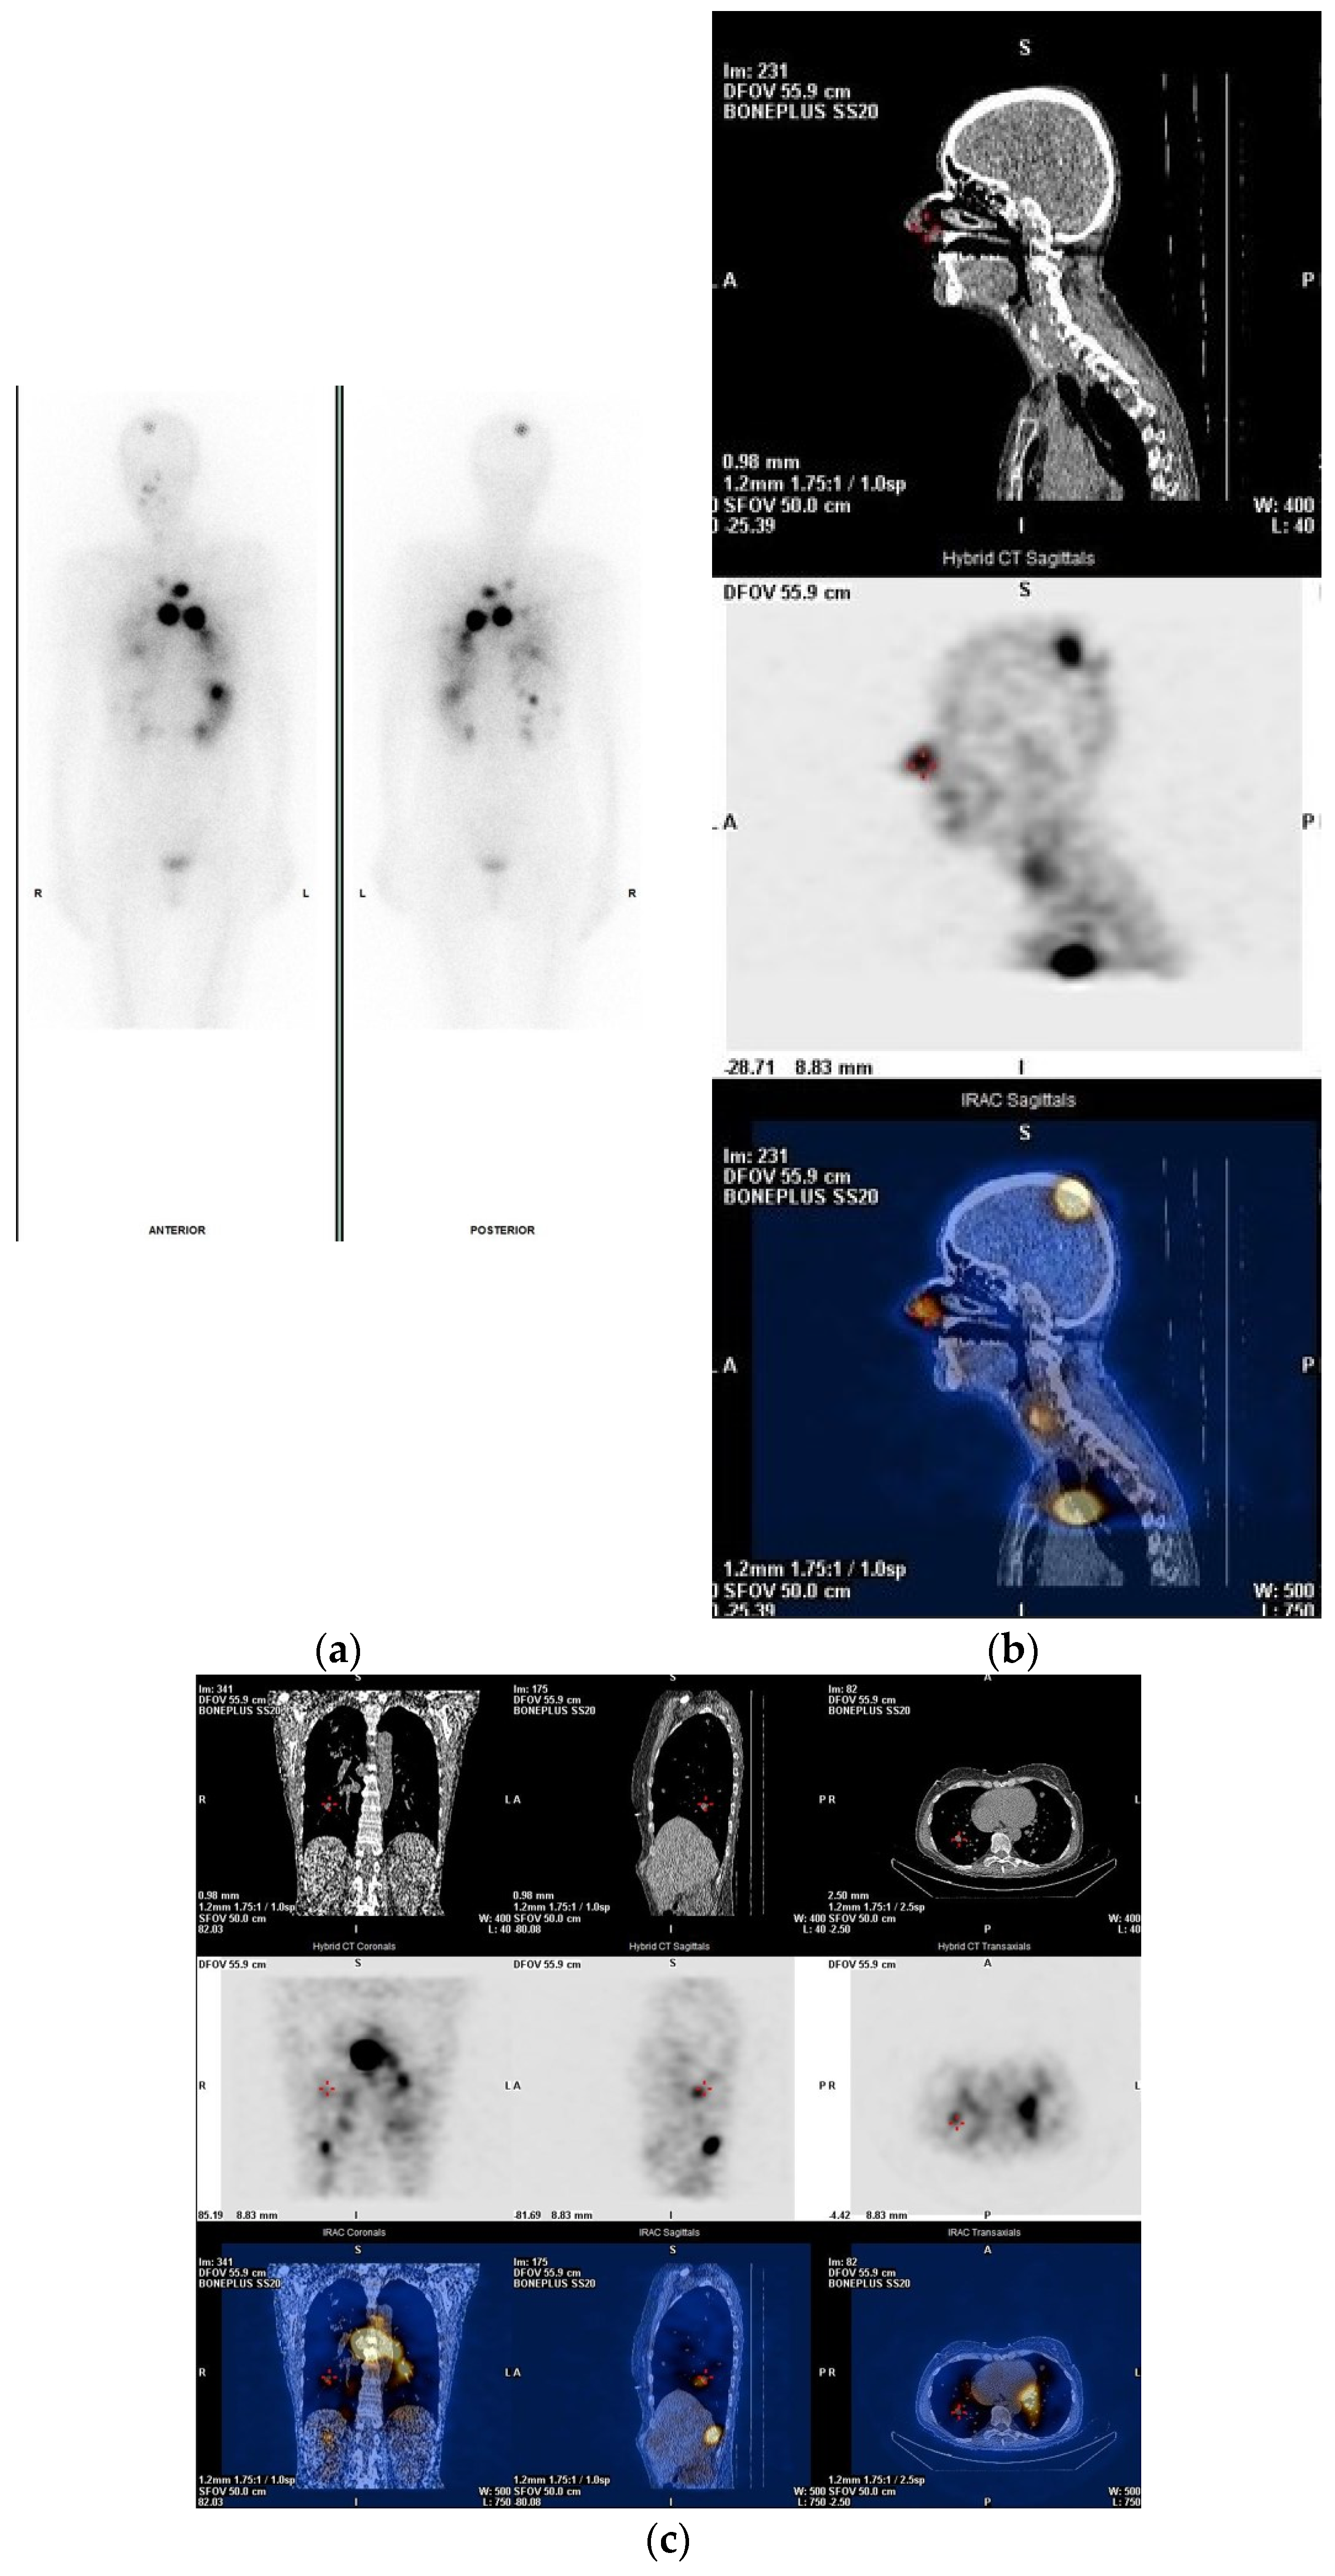

2. Pre-Treatment Whole-Body Imaging

3. Post-Treatment Whole-Body Imaging